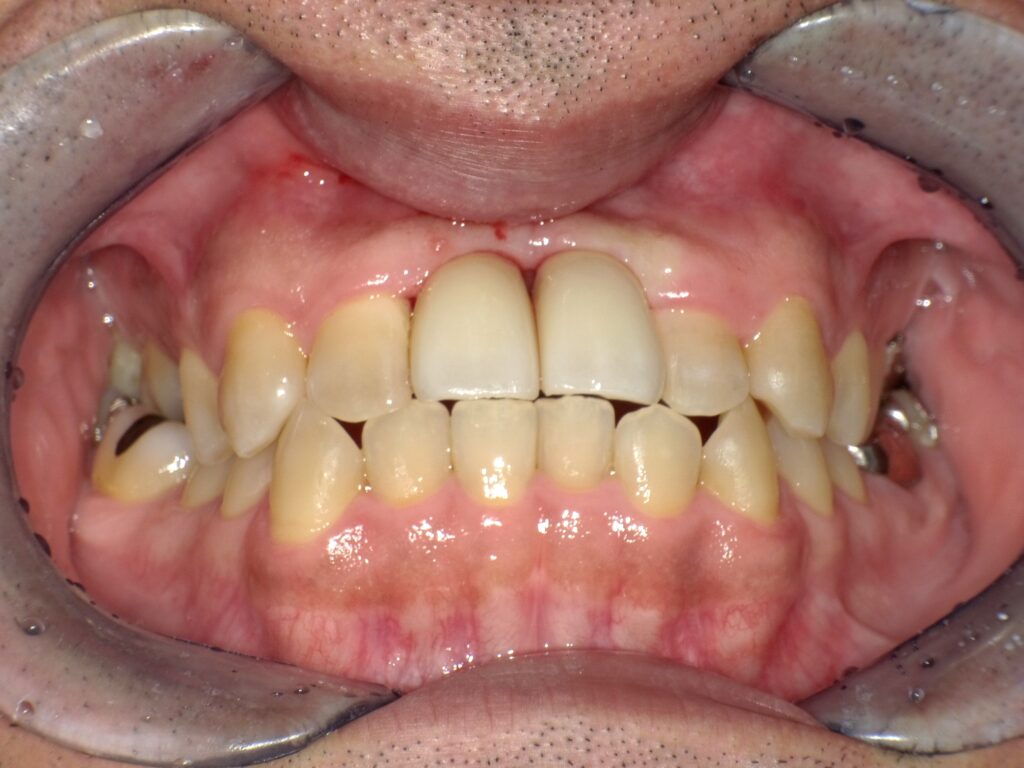

症例一覧 インプラント症例3 2024.11.25 治療内容インプラント主訴前歯部折れたのでインプラント治療を行いたい費用¥1259,500(2本)治療期間治療期間 7ヶ月 インビザライン症例1 前の記事 インプラント症例2 次の記事